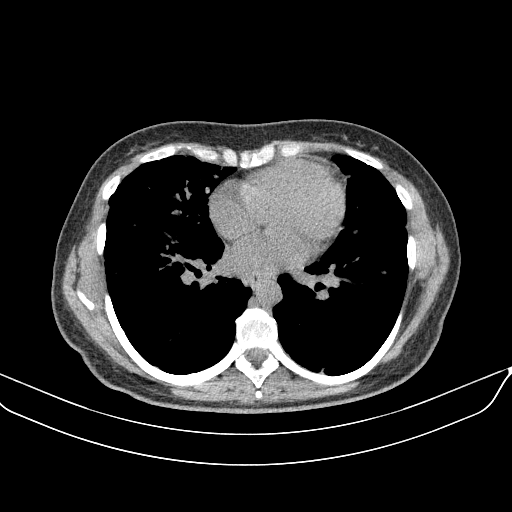

Image Grid

4Γ—3 grid: Rows show different image types (Original NATIVE, Reconstructed NATIVE, Original VENOUS, Generated VENOUS), Columns show windowing techniques (No Window, Lung Window, Mediastinum Window)

Original NATIVE CT scan (input)

Full window (WL 1023.5, WW 4095 β†’ Low βˆ’1024, High +3071)

Generated VENOUS CT scan (A→B translation)